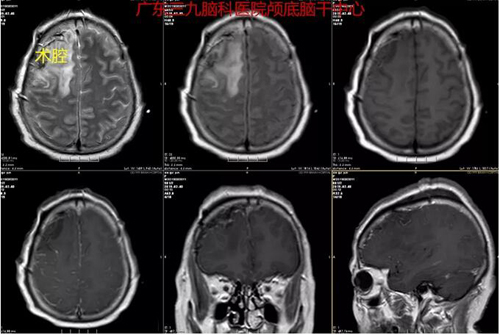

图3:术后MR示原病变已切除